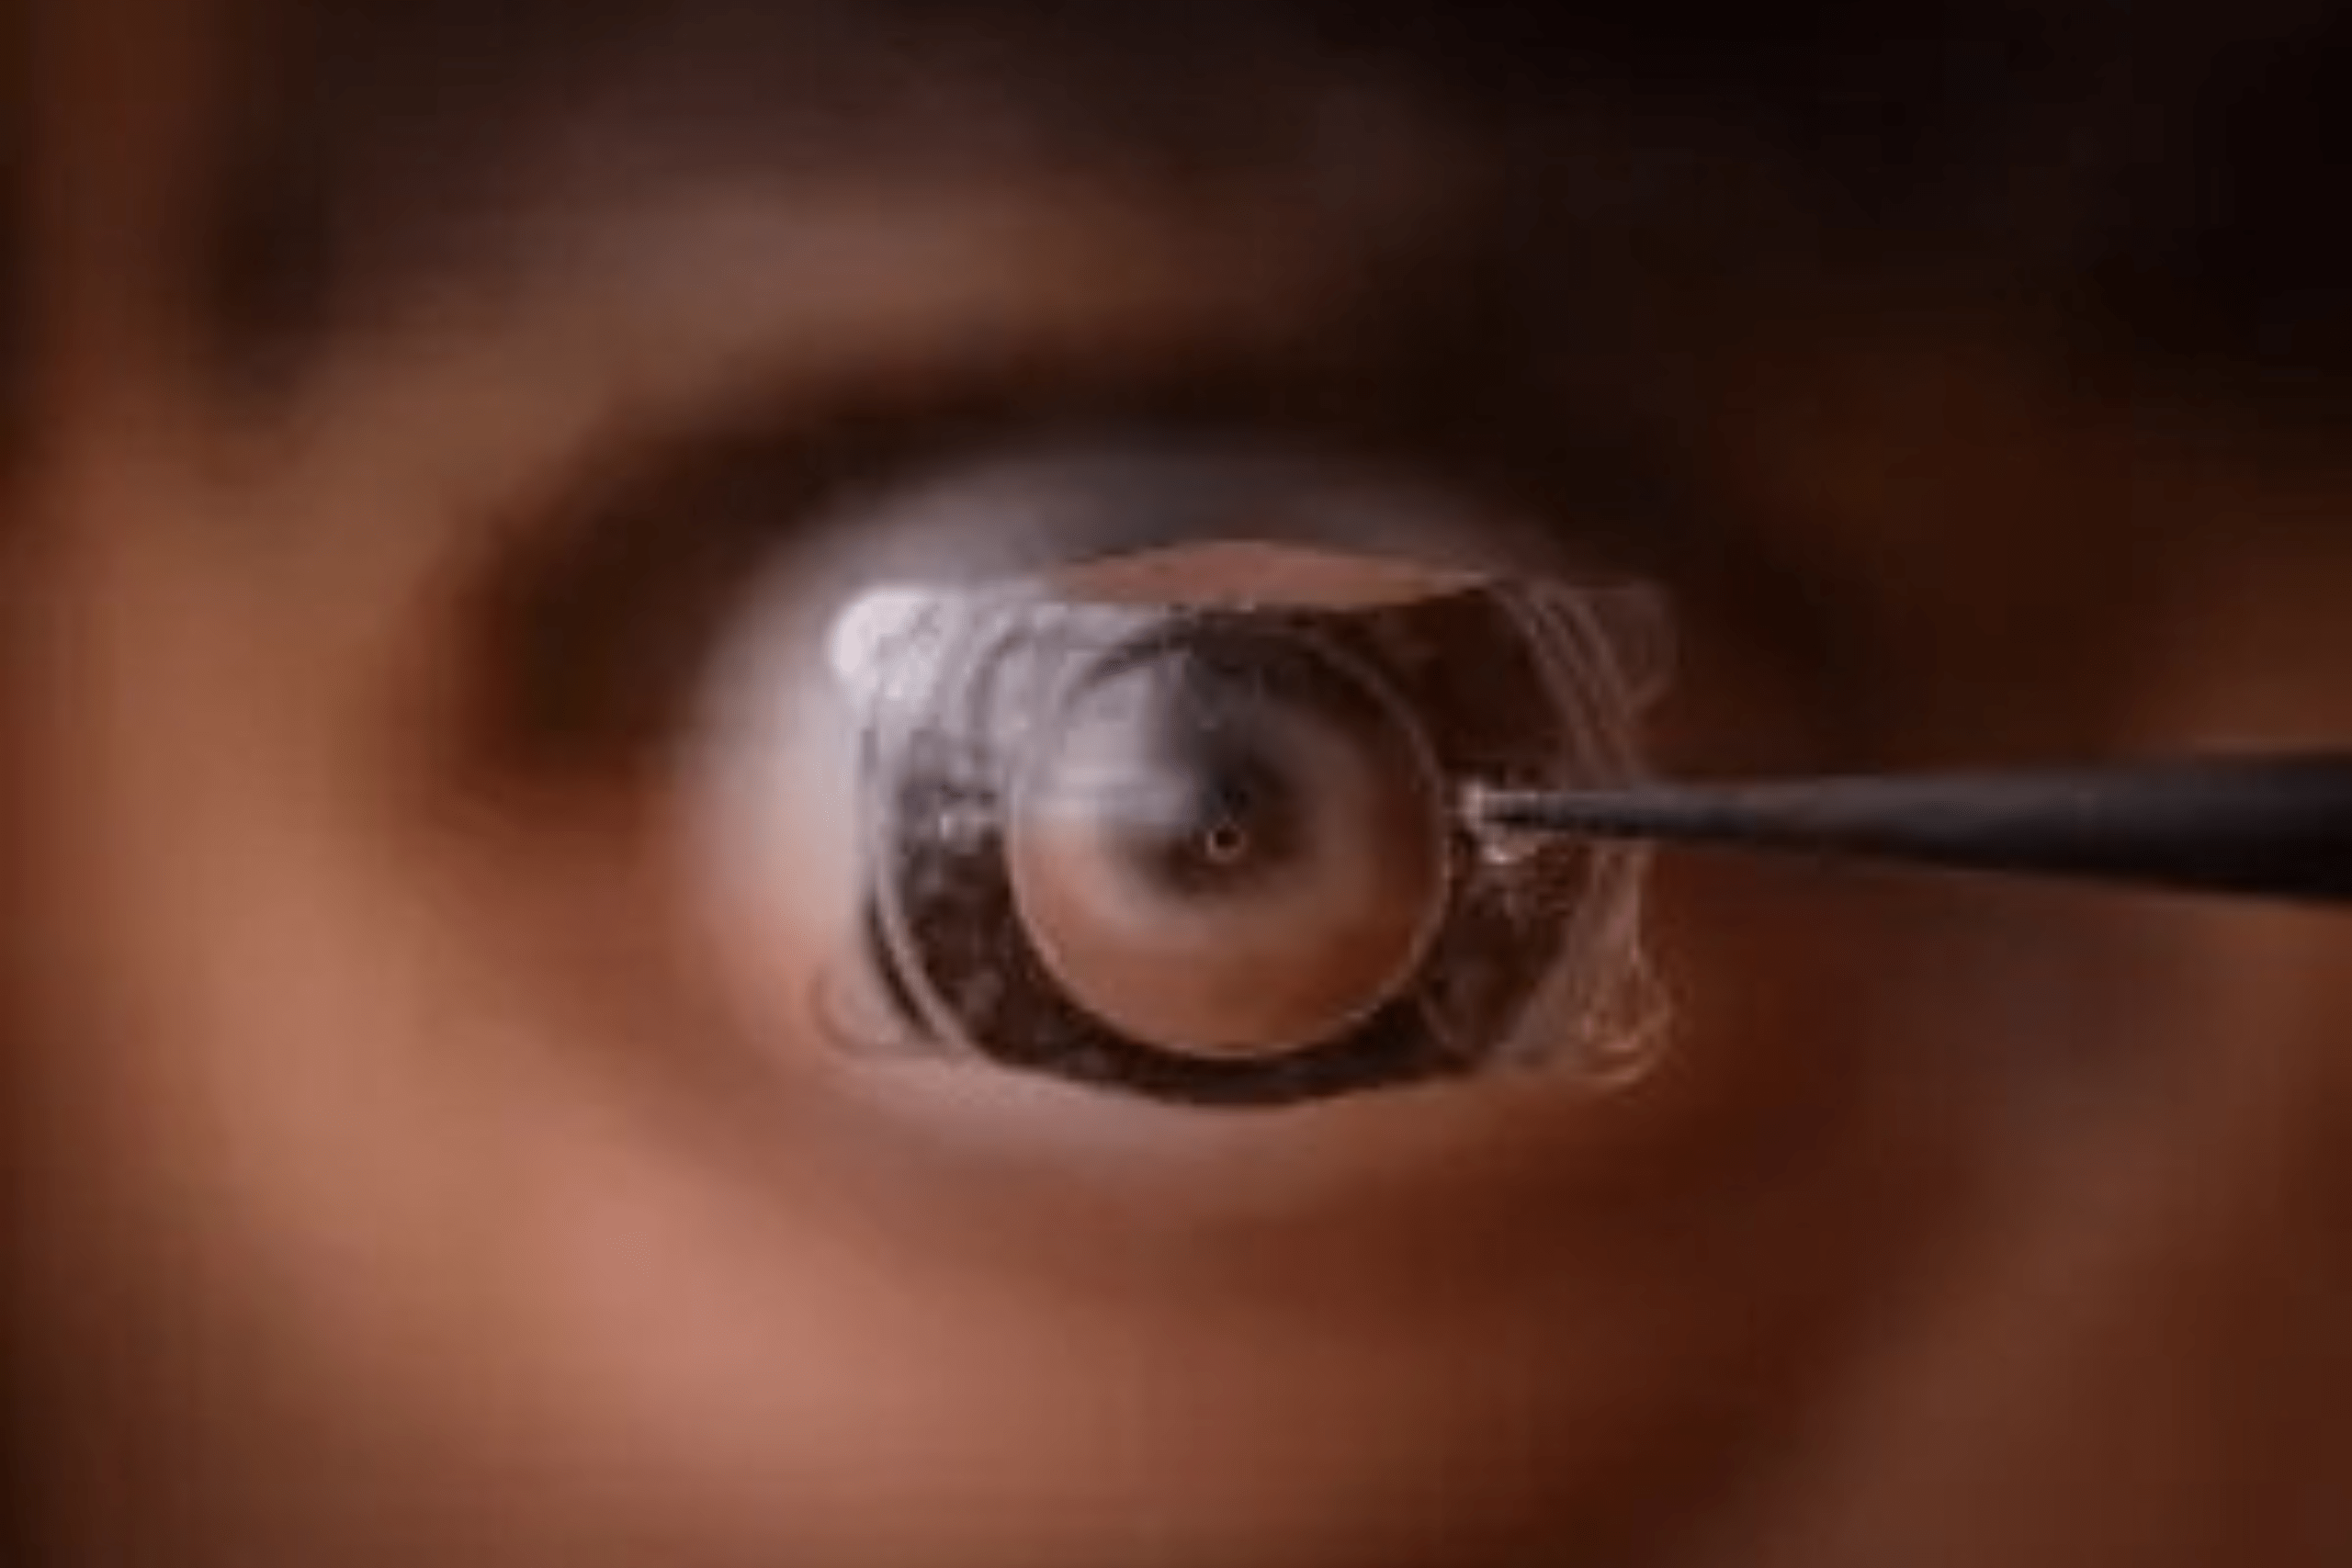

ICL surgery, or Implantable Collamer Lens surgery, is an advanced vision correction procedure designed for people with moderate to severe myopia (nearsightedness), hyperopia (farsightedness), or astigmatism. Instead of reshaping the cornea like LASIK, ICL involves implanting a soft, flexible, biocompatible lens between the iris and the natural lens of the eye. This lens helps to correct refractive errors and improve vision clarity without removing any natural eye tissue.

- Soft, Biocompatible Lens Implant